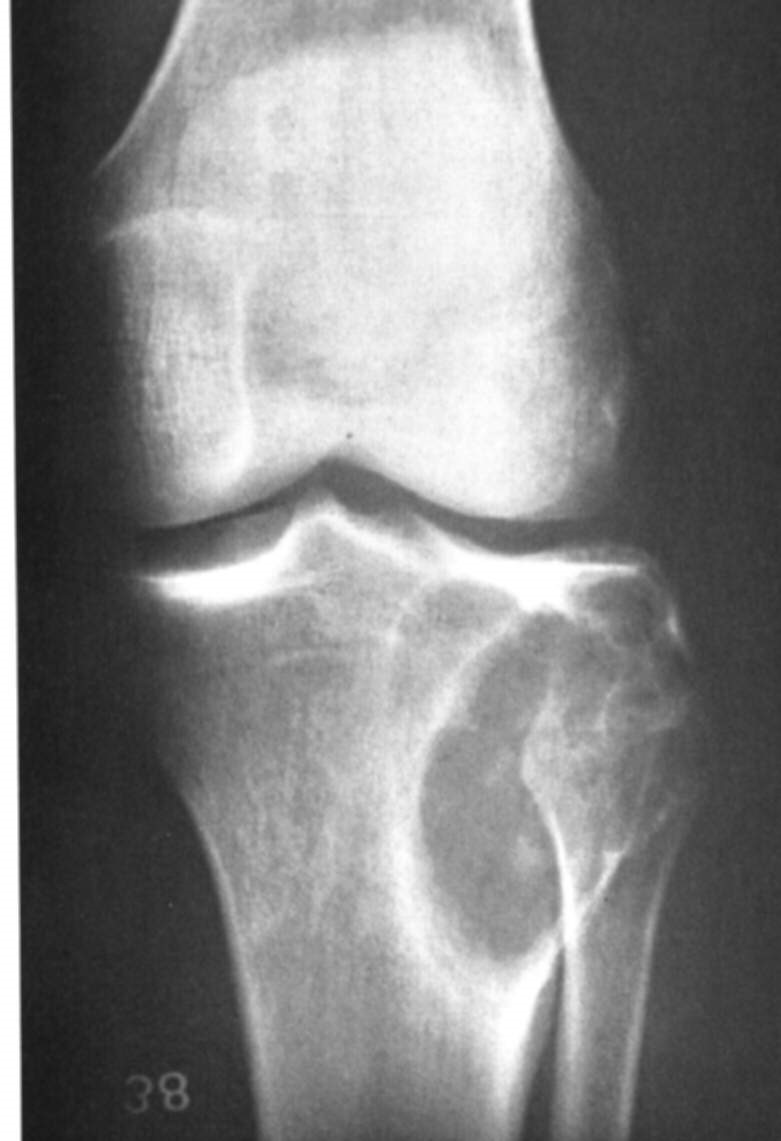

These tumors occur in small children and young adults, 10-20 years. Patient’s present with pain, fever may be present, and there may be local swelling and warmth. Lab tests show an increase in ESR, WCC and anaemia. Characteristically the flat and axial bones are involved. Visceral, lymphatic and meningeal involvement can occur.

Imaging

X-rays show a large destructive lesion that often involves the metaphysis and particularly the diaphysis (unlike osteosarcoma), they may be lytic, or show variable amounts of new bone formation. The periosteum may be lifted off in many layers, giving the uncommon but characteristic onion skinning. There is usually a large soft tissue component,(CT and MRI). A bone scan/PET is necessary to look for other bone involvement.